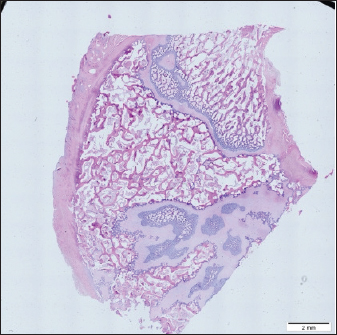

To get a comprehensive histological image of the sample, we had to merge all views into a single image using the Olympus Cell-Sens Dimension software (Fig. 2).

Fig. 2. Merged histopathology sample.